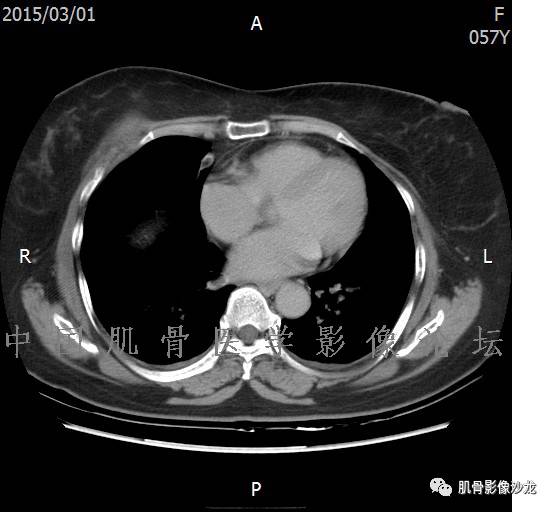

患者2月前无明显诱因下感右腿疼痛、麻木,疼痛呈持续性,发作时无法行走,休息后可缓解。当时无明显肿块,患者遂至当地医院就诊,查X片见右髂骨骨质破坏。6周前患者自觉右髋部渐大肿块,初肿块较小,后肿块逐渐增大,现肿块约12*10cm大小,有压痛。患者遂至我院就诊,查MRI:右髂骨异常信号,伴软组织肿块。ECT、肺CT未见转移。现患者为求进一步治疗,门诊拟“右髂骨肿块 ”收治入院。 患者发病来,神清,精神可,胃纳夜眠可,二便无殊,体重无明显变化。

1、软骨肉瘤可以有膨胀性骨质破坏(病例3,4),可以有溶骨性骨质破坏(病例2),局部皮质因为破坏变薄,中断 ;

2、软骨基质T2WI高信号,软骨小叶分叶状,也就会出现高老师提到的骨内膜扇贝形压迹。一般认为骨内膜扇贝形压迹超过骨皮质厚度的2/3是软骨肉瘤在长管状骨的特征性表现。如上图。3、软组织肿块或肿胀;

4、 钙化,环形,弓形,边缘模糊 ;

5、增强后进行性延迟,不均匀分割状强化, 会强化的纤维间隔,软骨小叶不会强化,关于老师们说到的钙化,软骨肉瘤不一定会有钙化 。